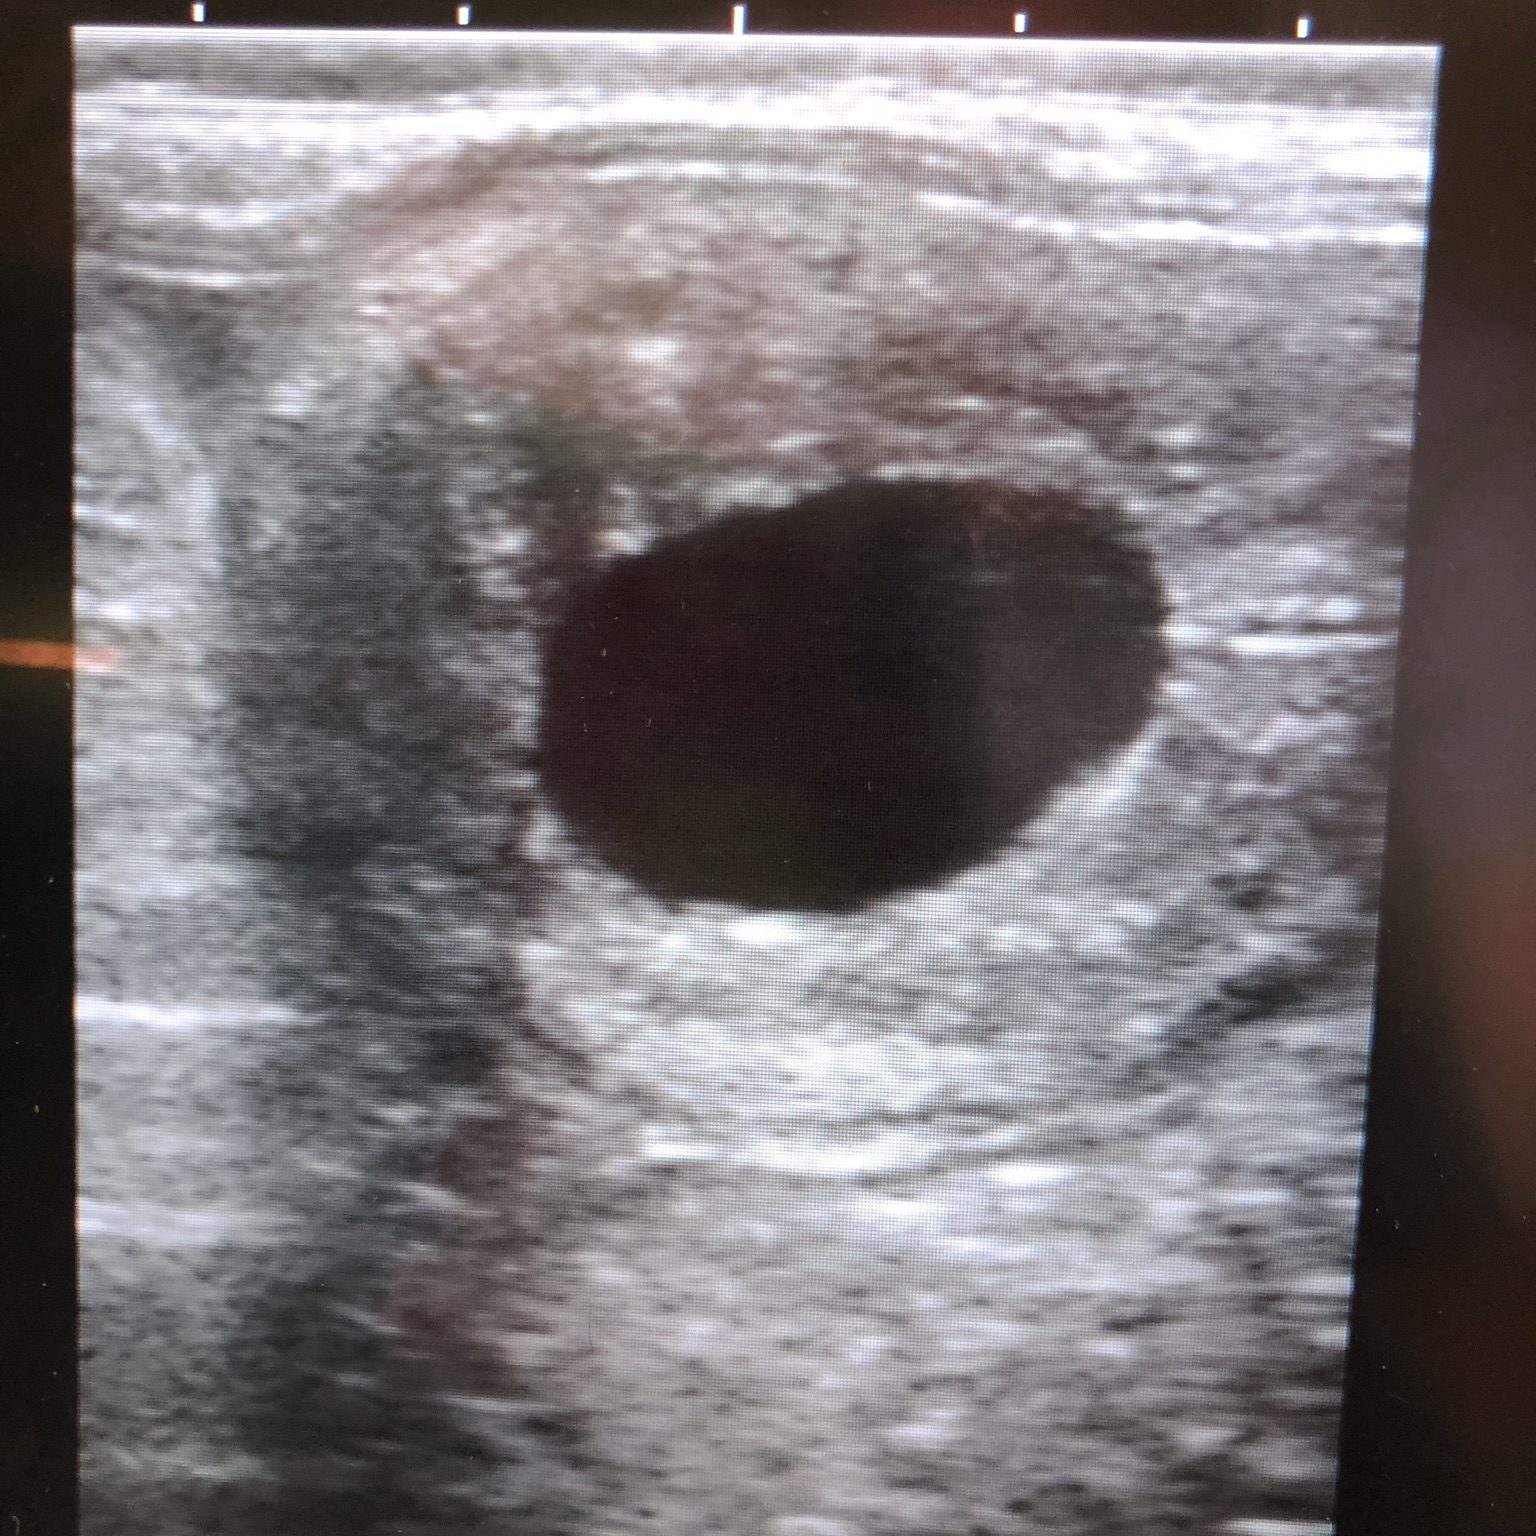

Auch in der Gynäkologie spielt der Einsatz von Ultraschall mittlerweile eine wichtige Rolle. Damit ist es möglich, den Bedeckungszeitpunkt exakt zu bestimmen und somit die Trächtigkeitsrate zu optimieren. Weiterhin kann eine Trächtigkeit ab dem 14.Tag verlässlich nachgewiesen werden und eventuelle Zwillingsträchtigkeiten können in frühem Stadium gemanagt werden.